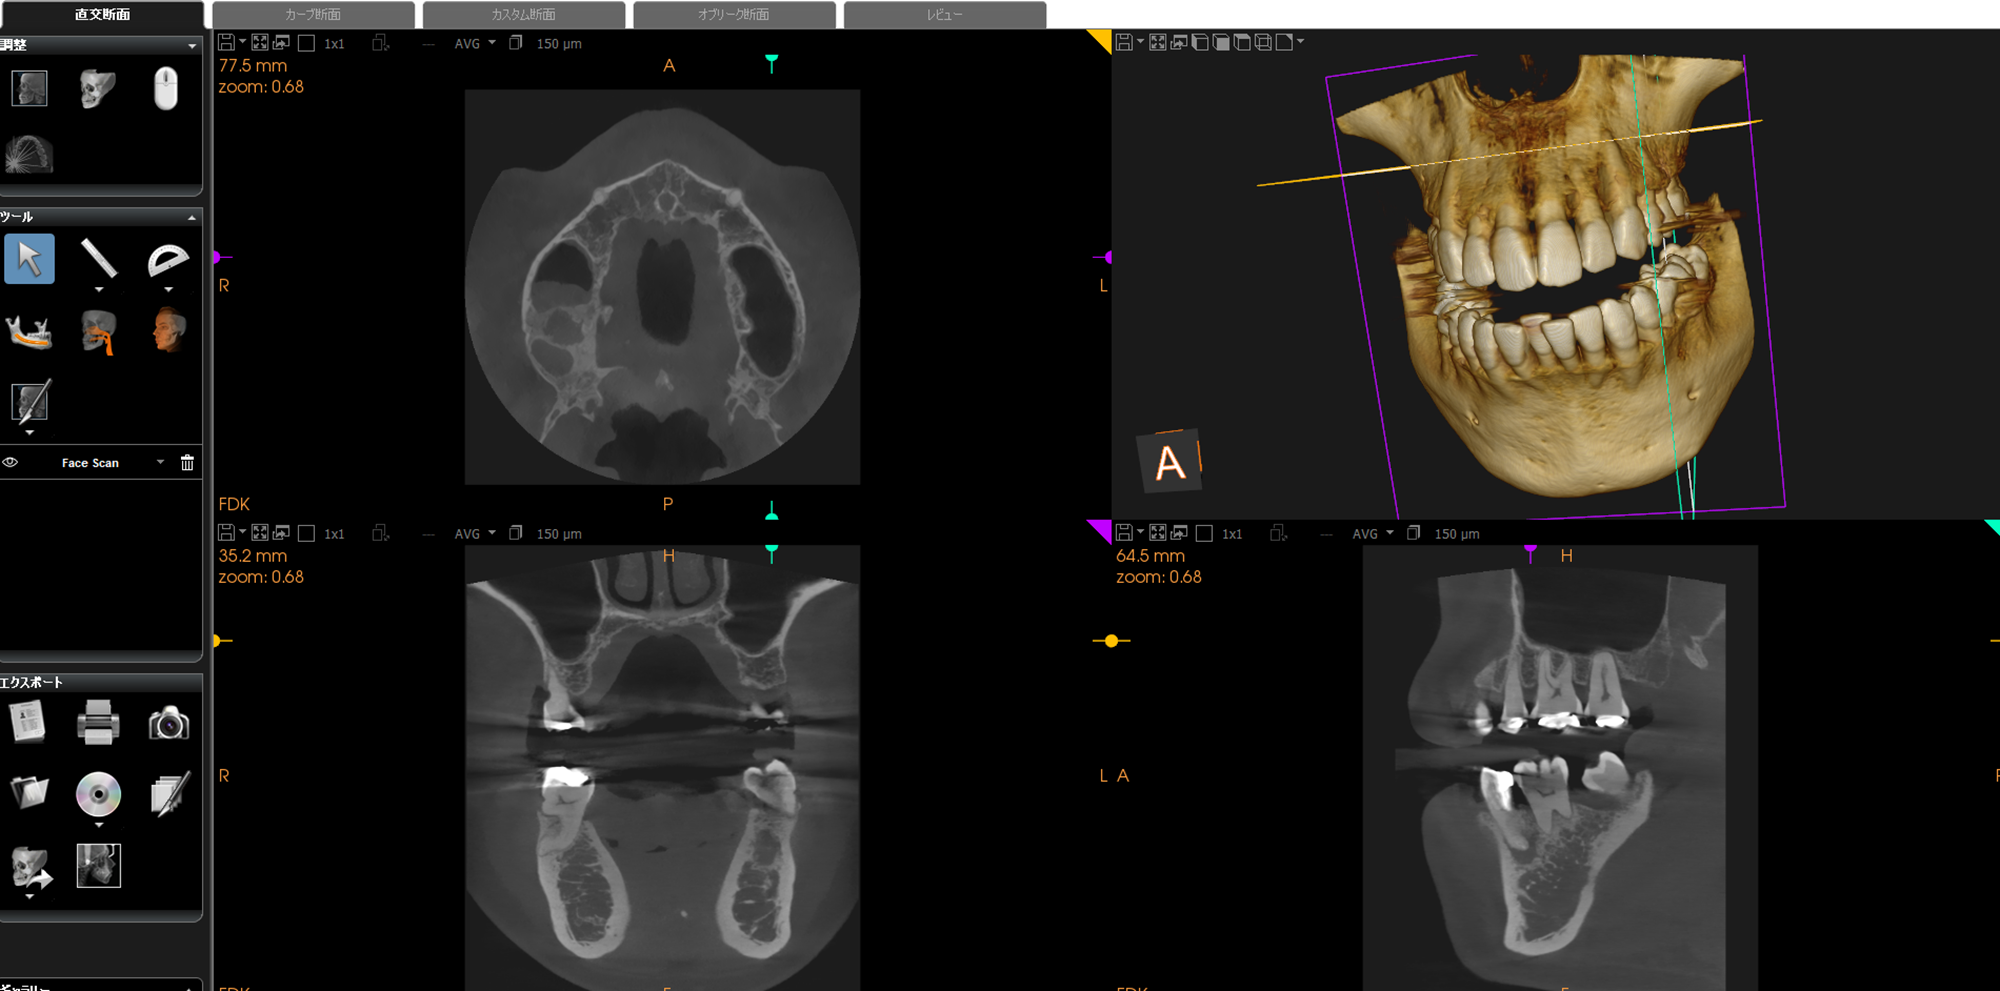

CTによる安全性の検査

歯科用CTを用いて、骨の量、神経、血管の走行を確認します。これにより安全性が格段に向上します。

シミュレーションによるわかりやすい説明

シミュレーションソフトを用いることで、1mm単位で正確な位置にインプラントを埋入します。神経、血管を損傷するリスクを極力低減します。